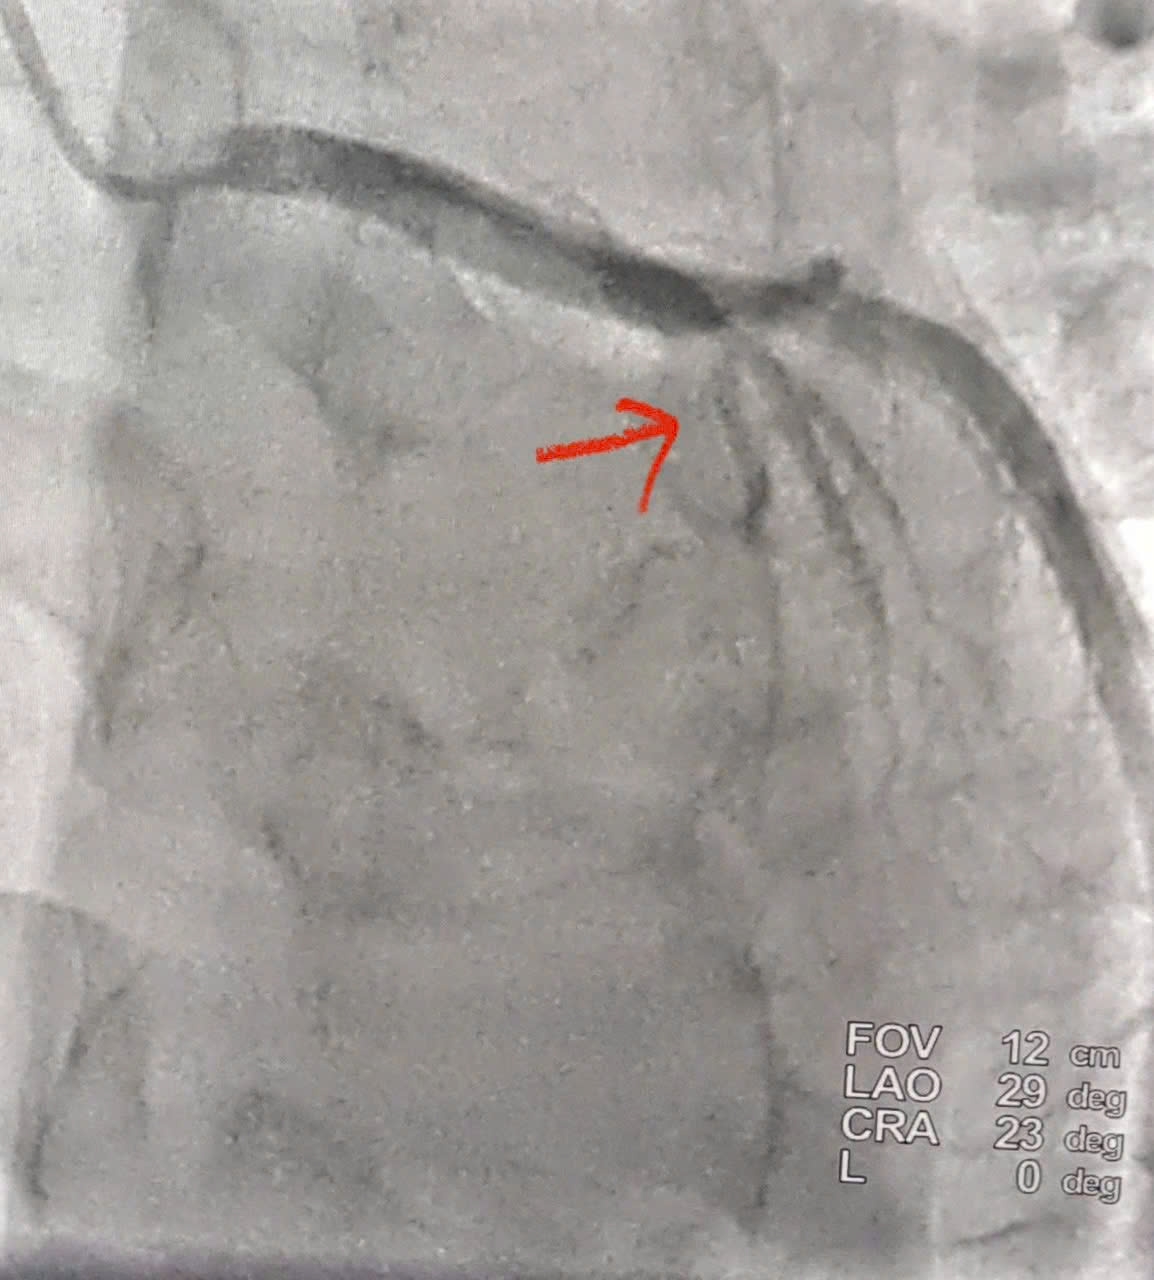

Kết quả chụp cho thấy tắc hoàn toàn động mạch liên thất trước đoạn II (LAD II) – nhánh mạch vành quan trọng nuôi phần lớn cơ tim thất trái. Ê-kíp can thiệp đã nhanh chóng tiến hành nong bóng và đặt một stent phủ thuốc tại vị trí tổn thương. Sau can thiệp, dòng máu được tái lập ngay, cải thiện rõ rệt tình trạng thiếu máu cơ tim.

Hình ảnh động mạch vành được tái thông sau điều trị tại Bệnh viện đa khoa Nghệ An